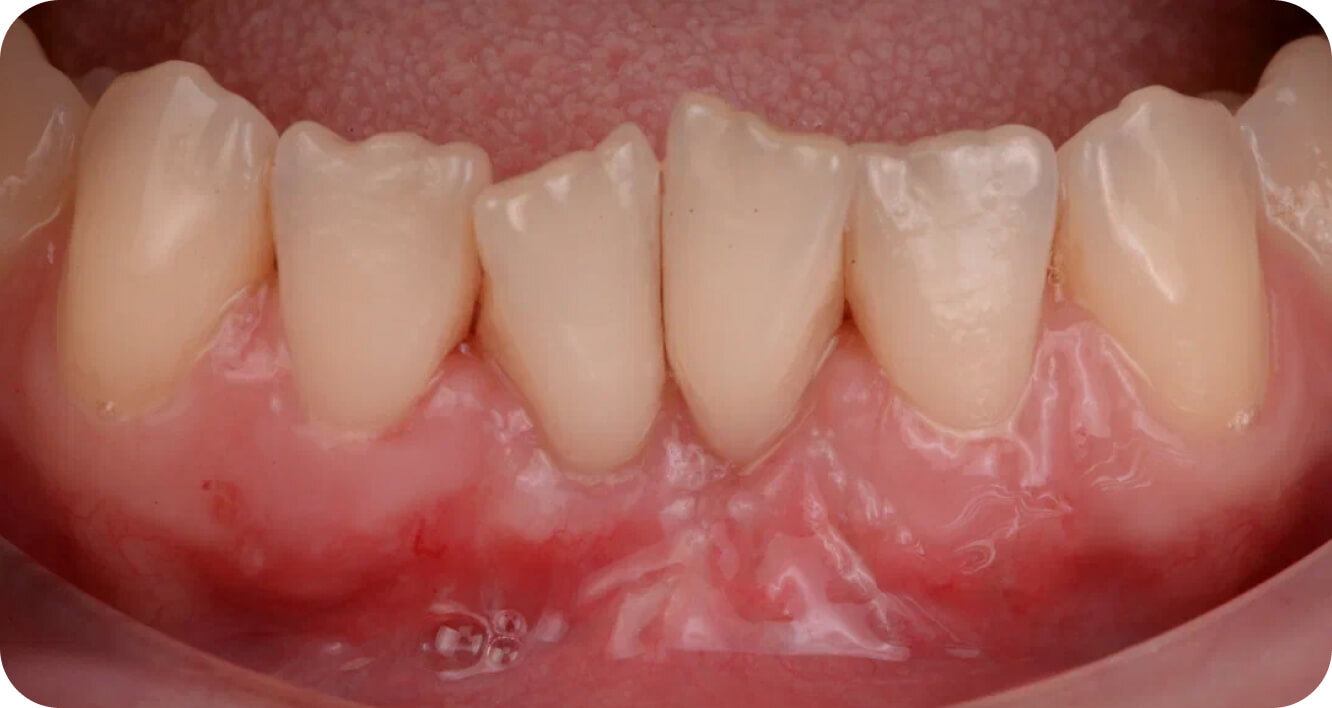

Пластика десны

оголенных корней

Пластика десны для закрытия оголенных корней зубов

Диагностика, планирование методики трансплантации мягких тканей при рецессии десны на зубах для закрытия оголенных корней.

Что входит в манипуляцию:

Окончательная стоимость манипуляции утверждается по данным 3д рентгена. Только после консультации.